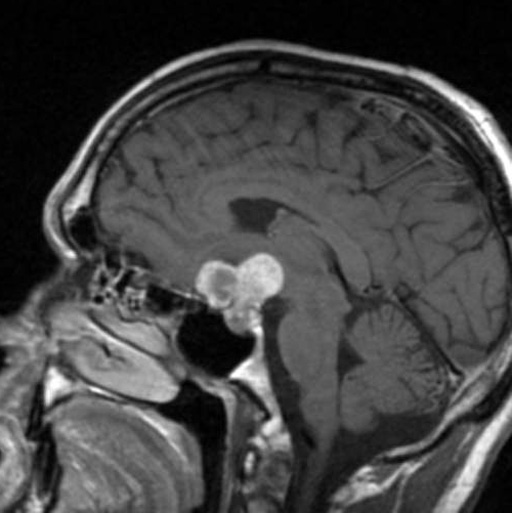

颅咽管瘤是一种少见的中枢神经系统(CNS)良性肿瘤,被认为是由脑垂体附近的Rathke's囊残余形成。它们占全部原发性中枢神经系统肿瘤的不到1%,但却是儿童常见的颅内非神经胶质肿瘤。颅咽管瘤能活多久?手术切除率与延长生存期相关。

颅咽管瘤是出了名的难治。这些组织学良性肿瘤位于蝶鞍及其周围,该区域与脑下垂体、下丘脑和视器有着密切的联系。因此,患者常表现为内分泌异常、视觉功能障碍或因临近三脑室而出现脑积水症状。尽管对这些病变进行了显微外科和内镜切除,GTR仍可能与内分泌病和神经系统疾病的风险相关。22为了避免不可逆的手术相关疾病,保守的手术策略,包括计划的STR和辅助放射治疗,正被越来越多地采用。然而,与目前流行的治疗模式一致的是,多数诊断为颅咽管瘤的患者较初是通过手术治疗的,通常以较特放射治疗为目的。